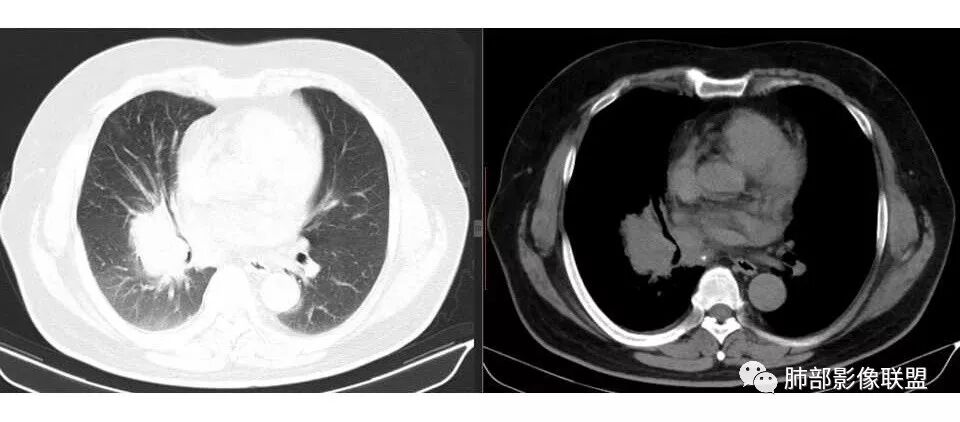

肺门及纵隔多发淋巴结。2L,4R,3区都有肿大淋巴结。

南边:有老师认为,血管前的这个应该是一个胸腺来源的。我觉得不是,为什么不符合胸腺来源呢,就看那个内乳动脉

双侧对比:右侧增粗,提示供血

但在内侧,不是外移

所以我倾向于淋巴结可能

胸腺瘤按理推压外移的多

而且胸腺癌转移不以淋巴结为主,如果淋巴结显著,按理周围侵袭性比较强,淋巴结也应该以附近为主,不应该以肺门为主,不符合引流规律。

南边: 而且肺癌,一定受叶段的局限,这一例跨越右肺门,提示多个淋巴结融合

南边: 例如这个病灶,如果是一个孤立的肿块,边界清晰,提示破坏性不强,不应该是包绕支气管,是推移到一边为主,这个表现为包绕,提示是多个病灶融合

1.右肺上叶不规则结节影,右肺门及纵隔多结节并形成巨大块影,密度均匀,沿途支气管明显狭窄。

原发灶小或隐匿,肺门纵隔淋巴结异常增大,所谓“娘小崽大”常见于肺小细胞癌!